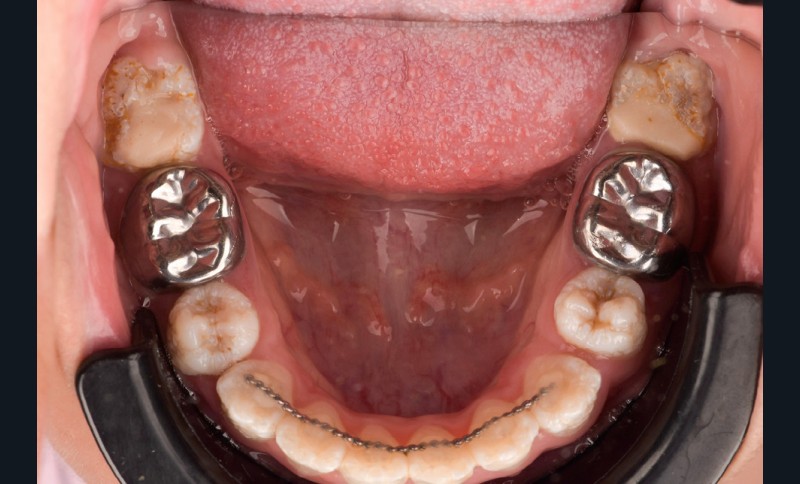

Lors de l’arrivée de la patiente, un examen clinique au fauteuil est effectué, complété par une empreinte numérique permettant l’enregistrement précis des arcades dentaires et de l’occlusion existante. Cet examen initial met en évidence une pathologie de type amélogenèse imparfaite. On note également la présence de couronnes métalliques au niveau des premières molaires, ainsi que de multiples restaurations, notamment au niveau des dernières molaires (fig. 1 à 4).